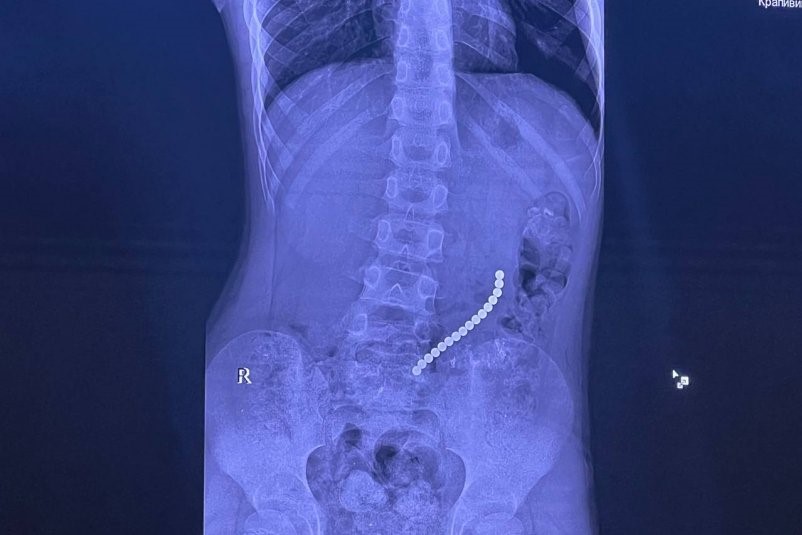

В Иркутской области врачи спасли 8-летнего ребенка, который проглотил несколько шариковых магнитов и получил серьезное повреждение внутренних органов. Об этом сообщает ИА IrkutskMedia со ссылкой на тг-канал (18+) главного врача, хирурга Юрия Козлова.

Мальчика привезли в областную больницу с жалобами на «острый живот». Врачи выяснили, что причиной стали инородные предметы, которые ребенок проглотил во время игры.

Несколько шариковых магнитов соединились между собой в разных сегментах внутренних органов и вызвали повреждение желудочно-кишечного тракта.

«Очень редкое сочетание: одни магниты находились в желудке, другие — в начальном отделе тонкой кишки. Это привело к образованию фистулы — сообщения между желудком и кишкой», — рассказал врач.